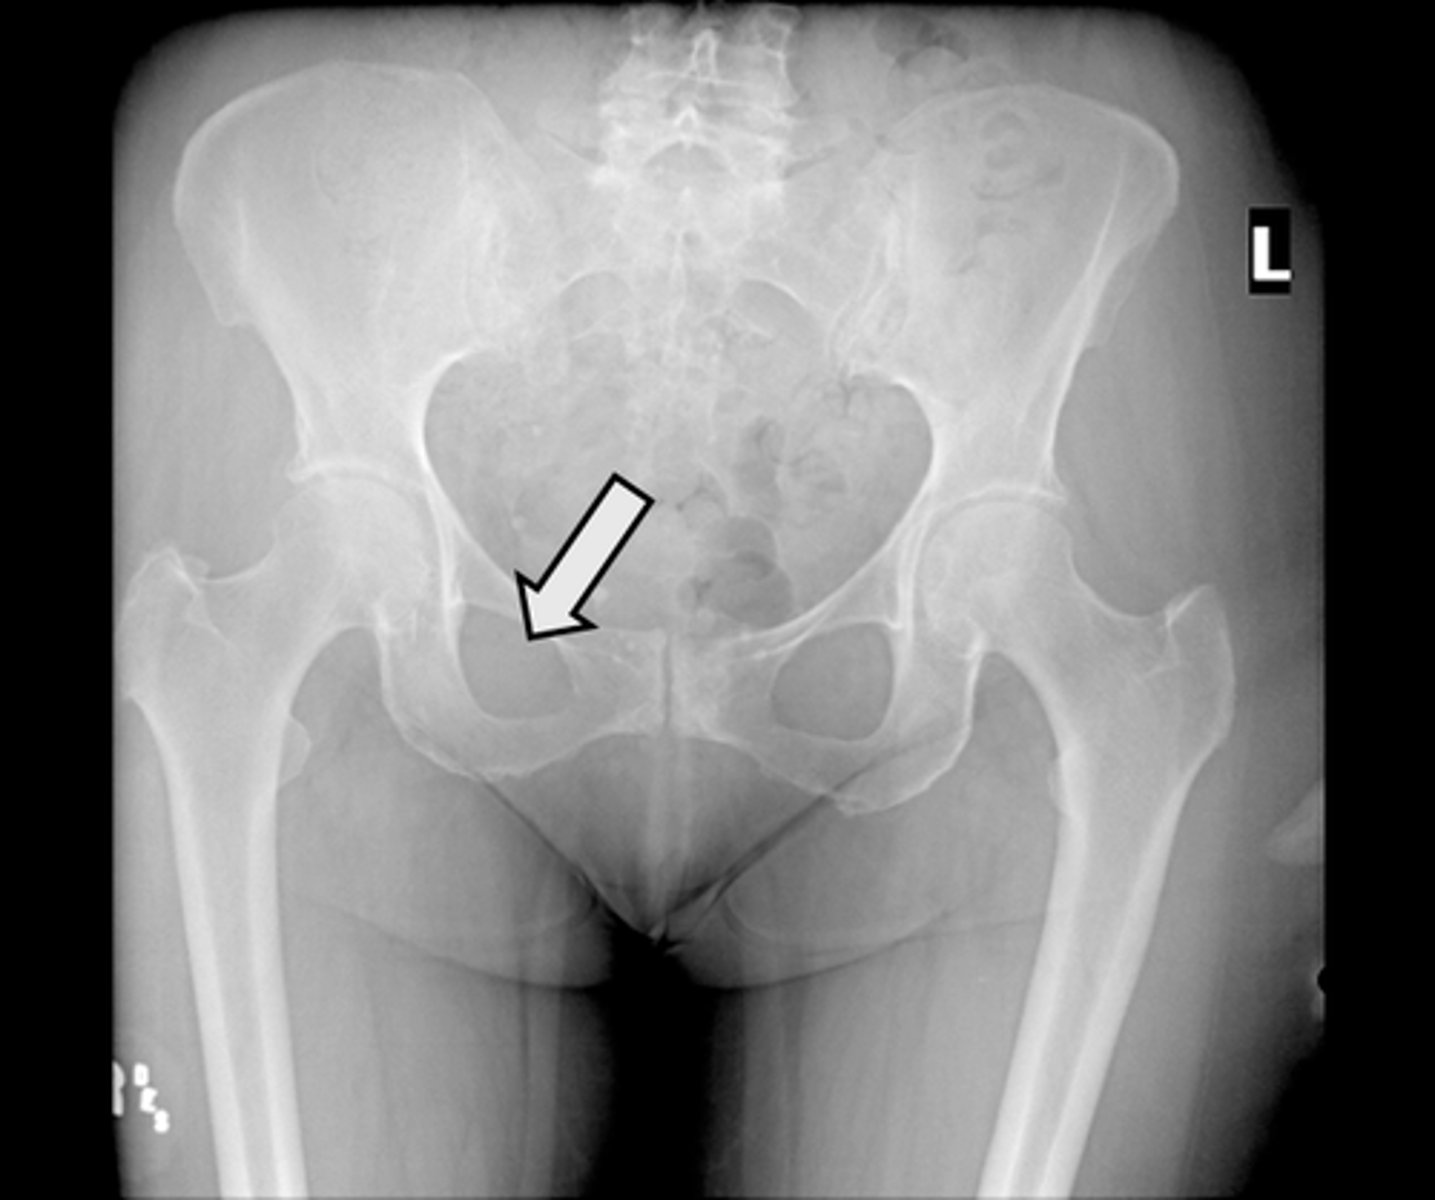

AP pelvis

What is the image?

<p>What is the image?</p>

2

New cards

Acetabulum

What is indicated in the image?

<p>What is indicated in the image?</p>

15

16

L acetabulum

17

L anterior superior iliac spine (ASIS)

18

L ilium

19

L ischial tuberosity

20

L obturator foramen

21

L sacroiliac joint

22

L superior ramus of pubis

23

R acetabulum

24

R anterior superior iliac spine (ASIS)

25

R ilium

26

R ischial tuberosity

27

R obturator foramen

28

R sacroiliac joint

29

R superior ramus of pubis

30

Sacrum